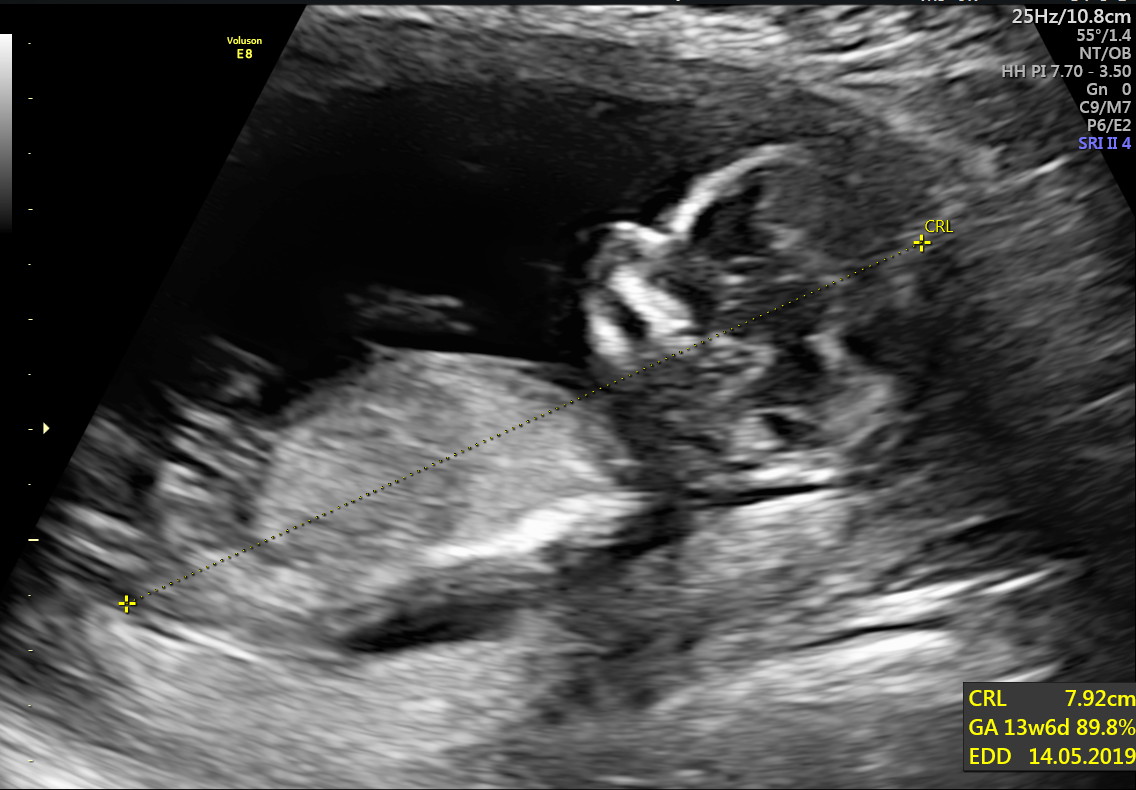

We have been home for a few weeks now and we're slowly adjusting to a somewhat normal life. Nah not really. Since being home we've started and finished a renovation, put our first home up for sale and found out we're expecting a bubba! We are beyond excited.

Thank you very much my friend. How are you?! I hope all is well in your world. Everything is progressing nicely at the moment. No morning sickness at all which has been nice ๐